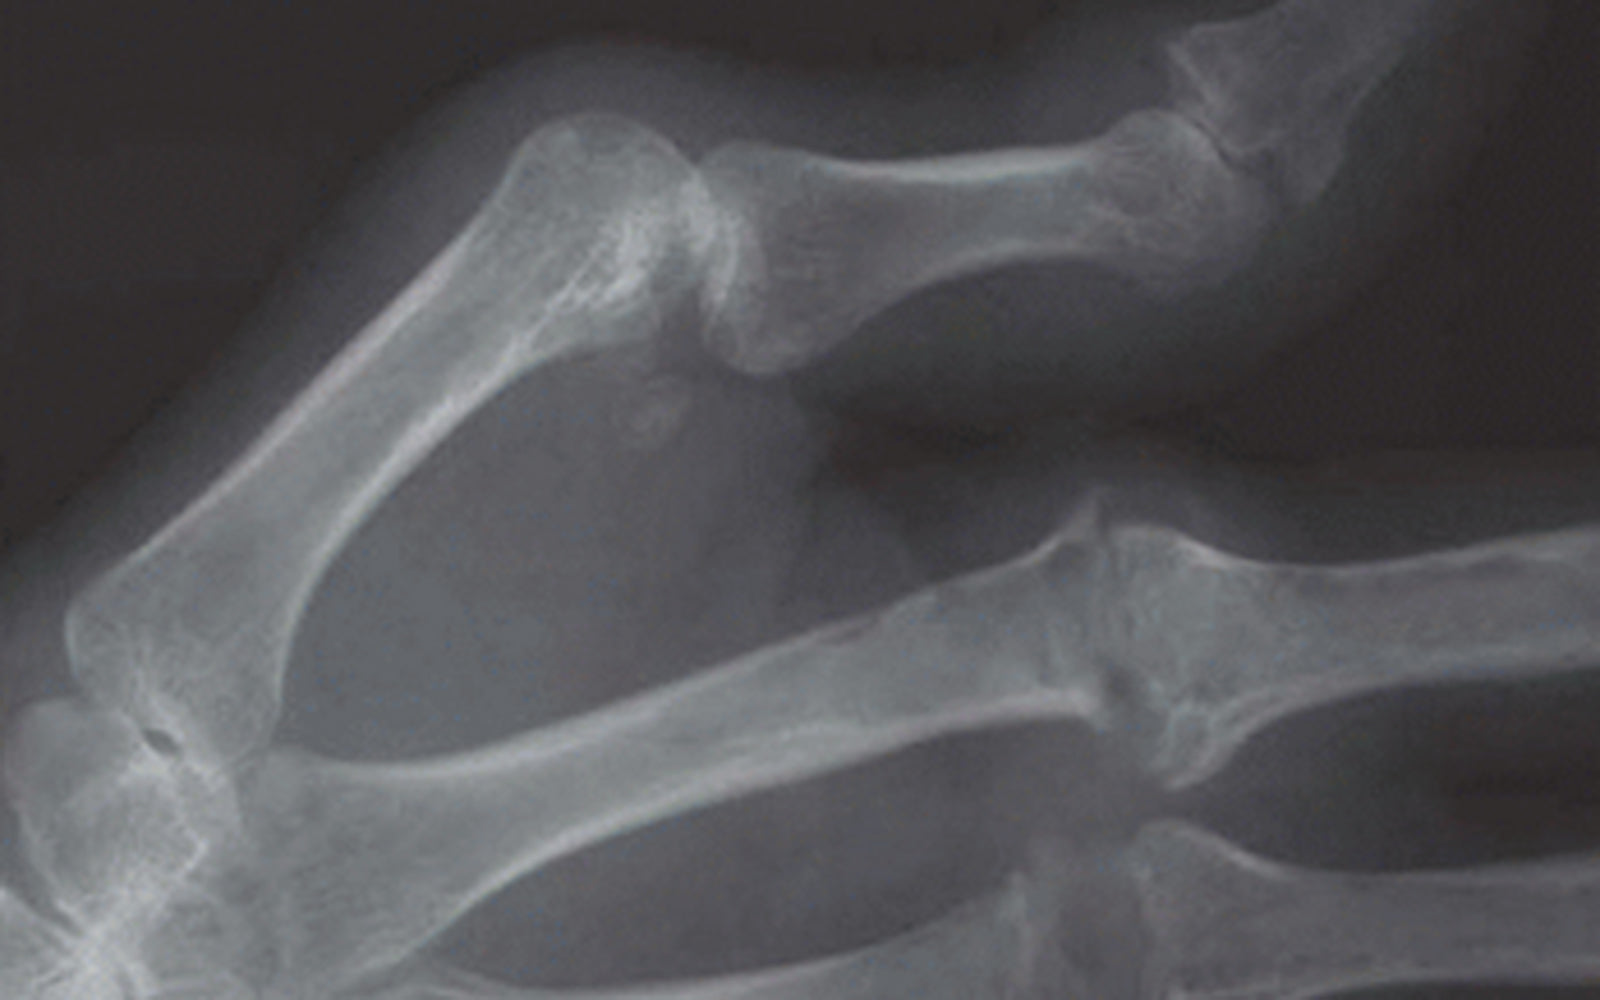

A Boutonniere deformity results from a Zone III extensor tendon (central slip) injury, and presents as PIP flexion and DIP hyper-extension.

It is caused by disruption of the central slip over the PIP joint, which can happen in several ways, such as laceration, closed rupture / traumatic avulsion (jammed finger), or capsular distension

(e.g. in rheumatoid arthritis).